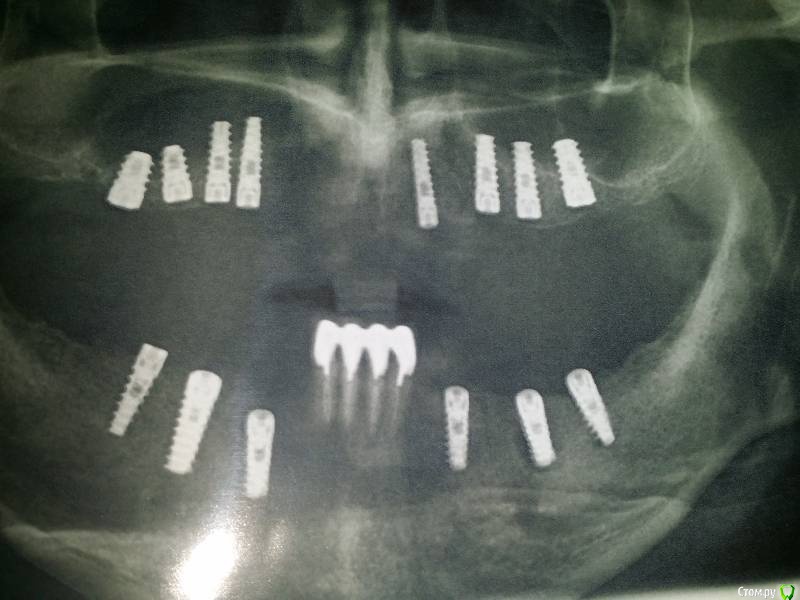

Zztop90 Опубликовано 12 марта, 2018 Поделиться Опубликовано 12 марта, 2018 (изменено) Добрый день, вкраце, ситуация такая: весной 2017 ставил импланты, 6 вниз и 8 наверху, в Октябре поставили коронки. Спустя примерно 5 месяцев сходил в ближайшую стоматологическую сетевую клинику, так как снизу слева начали оголяться импланты (дискомфорта почти нет, болей нет нигде).хирург отправил делать КТ у них же, и дал заключение- что все 14 имплантов подлежат удалению, по причине того, что сверху несколько штук вкручено в пазухи, снизу же они стоят под плохим углом, и при нагрузке давят на кости, от чего та уходит, оголяя импланты, И все это приведет к тому, что импланты снизу просто выдадут, выломав кость, ну а сверху нахождение импланта в пазухе- хронический гайморит, как минимум, ну и скорое отторжение имплантов. Итого- полное удаление имплантов, лечение пазух, наращивание кости и установка новых. Опять полтора года мучений (до обморочного состояния боюсь простых осмотров) и трата денег, здоровья. Подскажите, можно ли по ортопанораме определить, настолько ли все критично? Снимок делал после установки имплантов, до коронок, Но врач же должен был заметить проблемы с пазухами, и не ставить конструкцию на проблемное место. З.ы. КТ делал в простудном состоянии, был насморк. После установки имплантов каких-либо проблем с носом не было. Приложу снимок, который делал до установки коронок. Скриншоты из КТ сделать, к сожалению, не могу, так как не совсем понимаю где искать проблемные места и не уверен, что смогу открыть программу. Изменено 12 марта, 2018 пользователем Zztop90 1 Ссылка на комментарий

Irouil Опубликовано 13 марта, 2018 Поделиться Опубликовано 13 марта, 2018 Конечно, нужно КТ. Из того, что видно: вероятнее всего на нижней челюсти можно обойтись десневой трансплантацией и адекватной формой протеза + тщательная гигиена, в первую очередь вокруг крайних имплантатов; на верхней челюсти сложнее, вероятно действительно крайние имплантаты частично проникают в пазухи. Надо смотреть КТ пазух БЕЗ ПРОСТУДЫ, то есть хотя бы через пару недель после стихания насморка. Очень многое зависит от ситуации в самом носу, от климата, в котором Вы живёте и т.д. 2 Ссылка на комментарий

Irouil Опубликовано 13 марта, 2018 Поделиться Опубликовано 13 марта, 2018 Нет, только один, тот что слева наверху и то, наверное, не до конца. Но вообще я Ваши первые скрины пересмотрел... Не вижу никаких срочных проблем в пазухе. Из-за того, что есть на снимках, я бы не предлагал ничего снять. Раз в год снимки переделывать и контролировать прогресс. Там где оголяется хороший парадонтолог может все вывести на надёжный прогноз. Учитывая монолитность конструкции, углы установки почти не помеха. С пазухами если будут проблемы, то имплантаты тут не причинами, а только оттягчяющими обстоятельствами могут быть. Устранив причину (раскрыв соустья пазух) Вы не вспомните про имплантаты. В общем, с приложенными данными, удалять ничего не рекомендую 2 Ссылка на комментарий